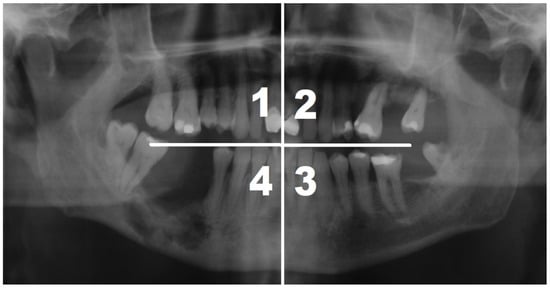

| MRONJ location | Maxilla quadrant | 1st | ![]() | 7 |

| 2nd | 9 | |||

| Maxilla total | 16 | |||

| Mandible quadrant | 3rd | 19 | ||

| 4th | 28 | |||

| Mandible total | 47 | |||

| Quadrant 1 (N = 7) | Quadrant 2 (N = 9) | Quadrant 3 (N = 19) | Quadrant 4 (N = 28) | p | |||||

|---|---|---|---|---|---|---|---|---|---|

| N | % | N | % | N | % | N | % | ||

| Complete remission | 6 | 86 | 5 | 56 | 9 | 47.5 | 9 | 32 | 0.2216 |

| No change | 1 | 14 | 2 | 22 | 9 | 47.5 | 11 | 39.5 | |

| Improvement | 0 | 0 | 2 | 22 | 1 | 5 | 6 | 21.5 | |

| Deterioration | 0 | 0 | 0 | 0 | 0 | 0 | 2 | 7 | |